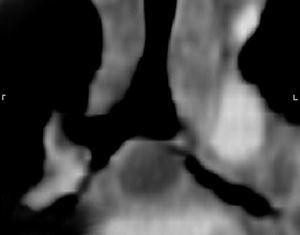

Se remite al paciente a otro centro donde se realiza fibrobroncoscopia confirmando los hallazgos de la broncoscopia virtual donde se observa reducción concéntrica del calibre de los bronquios principal izquierdo, lóbulo superior izquierdo y língula, desplazamiento de la pared medial de la pirámide basal izquierda, desplazamiento y distorsión del bronquio principal derecho e intermediario. Los bronquios del lóbulo superior y pirámide basal derechos eran normales (figs. 3 y 4).

Figura 3.TC con reconstrucción coronal. Adenopatías subcarinales que comprimen y distorsionan en bronquio principal izquierdo y bronquio intermediario derecho. Los bronquios del lóbulo superior derecho y de la pirámide basal izquierda se encuentran permeables y de calibre conservado.